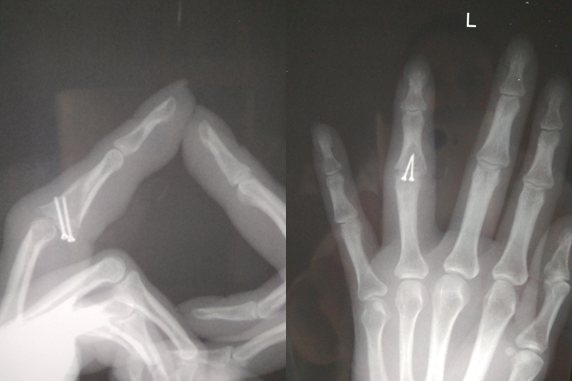

Девушка, у которой неправильно срослась фаланга пальца, вот так описала свои жалобы:

“Если рука в покое, в пальце тянущее ощущение где-то от середины ладони, он будто тяжелее остальных, или как-будто затёкший, это не беспокоит, просто заметно. При вибрации, встряхивании пальца больно от слегка до очень, например, если задеть рукой что-нибудь (не стукнуться, а легко) — за одежду зацепиться, рукой об руку, мебель — это уже больно, морщусь, но терпимо. Муж неожиданно за руку взял — аж вскрикнула, резкая боль. Держать в руке весомый (салатница, книга) предмет (4 пальца внизу большой сверху) больно, сразу перехватываю другой рукой. Разжимаю кулак после того как пакет из магазина принесу и пару минут перетерпеть надо пока боль утихнет — хотя нагрузка вроде больше на другие пальцы, и нести было не больно. При этом сгибать-разгибать палец больно, только если стараться сделать это с усилием, дальше, чем у него самого получается” (орфография и пунктуация автора сохранены).

На снимке отчетливо видно смещение по суставной поверхности средней фаланги, которое не было устранено при лечении перелома.

В данном случае корригирующая остеотомия невозможно и была выполнена пластика костно-хрящевым трансплантатом из крючковидной кости (hemi-hamate arthroplasty).

При этой операции берется кусочек кости с хрящом из крючковидной кости, который идеально подходит для замещения дефекта суставной поверхности основания средней фаланги.

Вот так выглядит палец после операции.